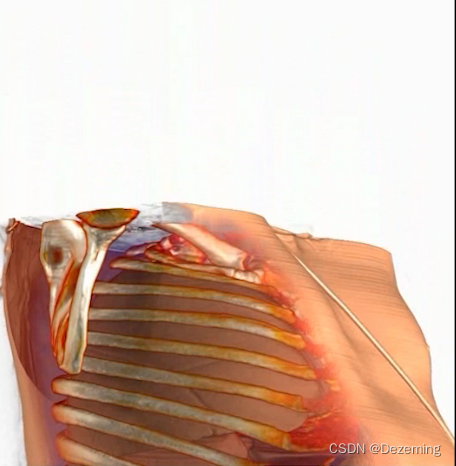

有一个医学影像视频,需要给小弟弟全都打码。这个医学影像视频里的视角还是不断移动的:

而且有些时候小弟弟会消失在视野里。